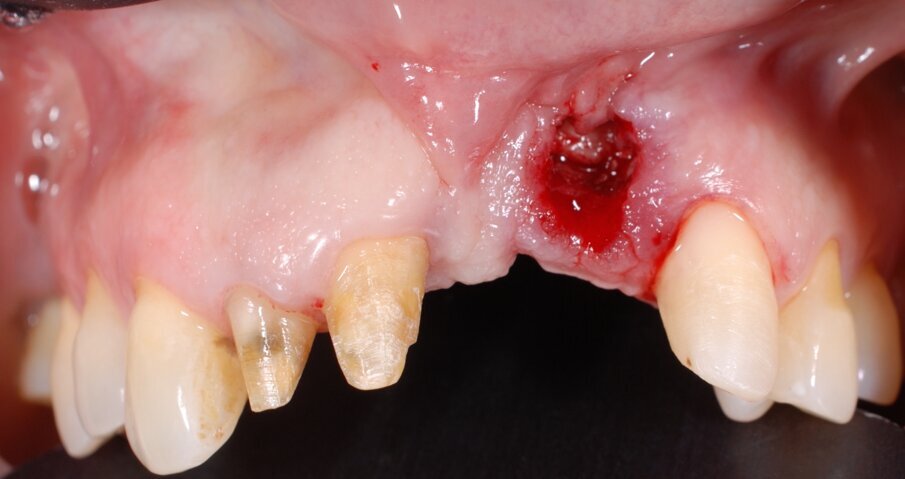

In questo articolo presentiamo un caso clinico che dimostra come il posizionamento improprio di un impianto può rendere impossibile la riabilitazione protesica, che richiede una nuova pianificazione chirurgica e riabilitativa per ottenere l’estetica desiderata. La paziente si presenta alla nostra osservazione con una riabilitazione protesica incongrua, con flangia in resina, a supporto dentale ed implantare, con la presenza di un impianto in posizione 2.1 vestibolarizzato e con l’emergenza nel fornice, in mucosa alveolare. Dalla valutazione della Tac si evince la posizione errata dell’impianto e la perdita consistente in senso trasversale della compagine ossea (Figg. 1, 2). Pertanto si opta per il seguente piano di trattamento che prevede: rimozione dell’impianto e preparazione protesica dell’elemento 2.3, confezionamento di un primo provvisorio a supporto dentale che servirà a guidare la guarigione dei tessuti (Figg. 3-7). A distanza di 4 mesi si procede a un innesto epitelio connettivale libero con prelievo dal palato per compensare il gap dei tessuti molli in senso trasversale, quindi viene ribasato il provvisorio in modo tale da favorire la guarigione dei tessuti (Figg. 8-11). A 9 mesi dalla maturazione dei tessuti si procede alla finalizzazione protesica fissa a supporto dentale (Figg. 12-14).

Fig. 3 - Rimozione del manufatto protesico che evidenzia la posizione errata dell’impianto in sede 2.1.

Fig. 4 - Visione occlusale dopo rimozione del manufatto protesico si noti la posizione errata dell’impianto.